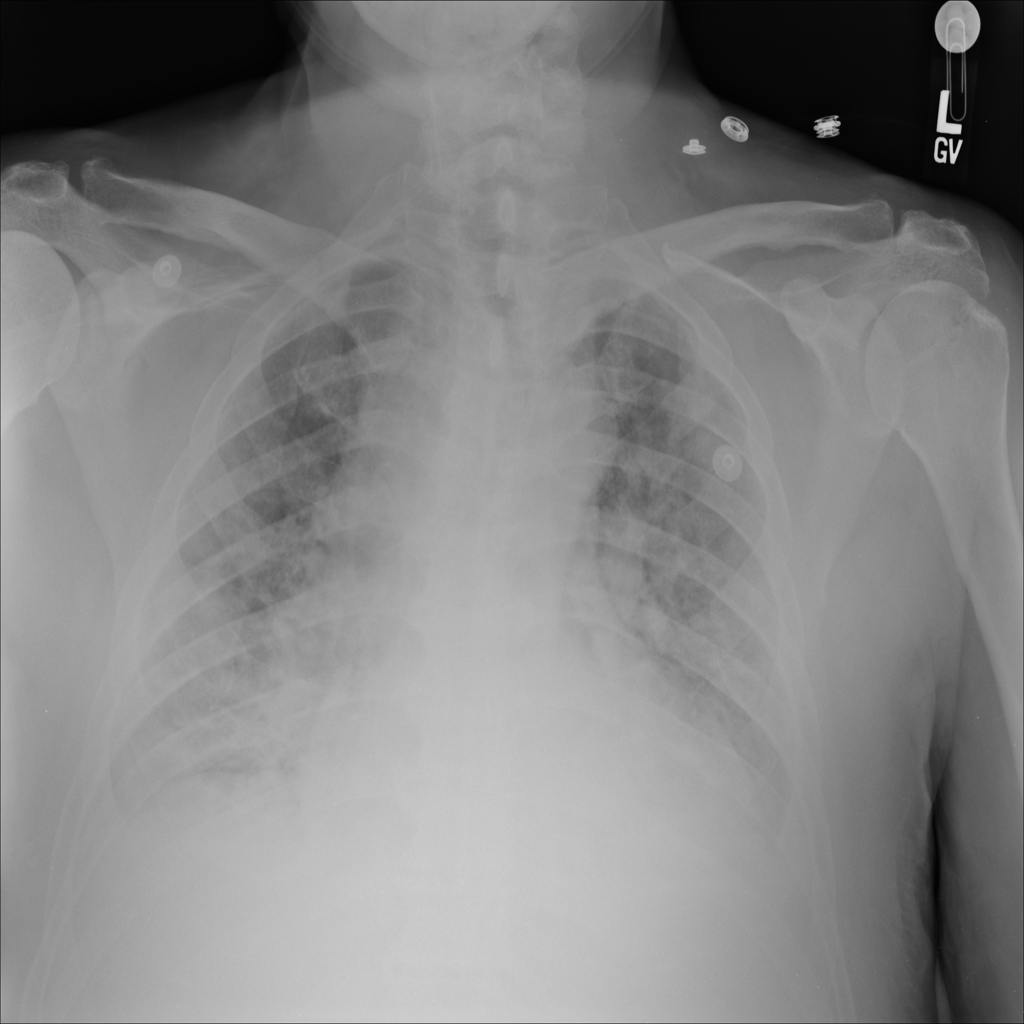

PAT-E828 · IMG-005Edema

PAT-E828 · IMG-005

AP